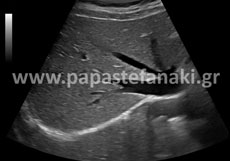

Υπέρηχοι άνω κάτω κοιλίας

Υπέρηχοι Ανω Κοιλίας